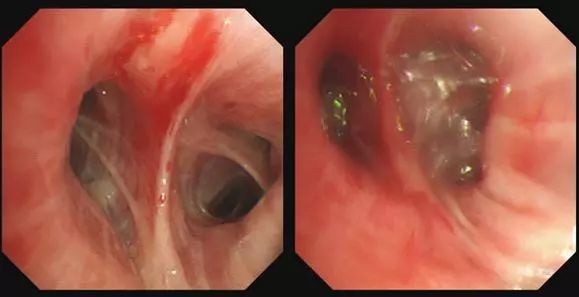

无创辅助通气下转运患者从呼吸监护室至气管镜室;持续无创呼吸机辅助呼吸下静脉推注丙泊酚40 mg至患者呈意识模糊(RASS -3~-4)状态,并摆平卧位;经无创通气面罩工作孔实施支气管镜介入治疗(图3),于右肺上叶尖、后、前段支气管开口置入4枚EBV(图4);基于对CT影像学的评估及缩短手术时间,未实施Chartis旁路通气检测;术中给予丙泊酚持续镇静(2 mg/kg/h),2%利多卡因局部麻醉;术中持续心电监测生命体征(心率、血压、呼吸频率和血氧饱和度),呼吸机持续监测呼吸参数(潮气量、分钟通气量、呼吸频率、呼吸波形),持续评估镇静状态;术后患者即刻清醒并辅助通气下安返病房。

图4 右肺上叶镜下术前(左)与术后对比(右)